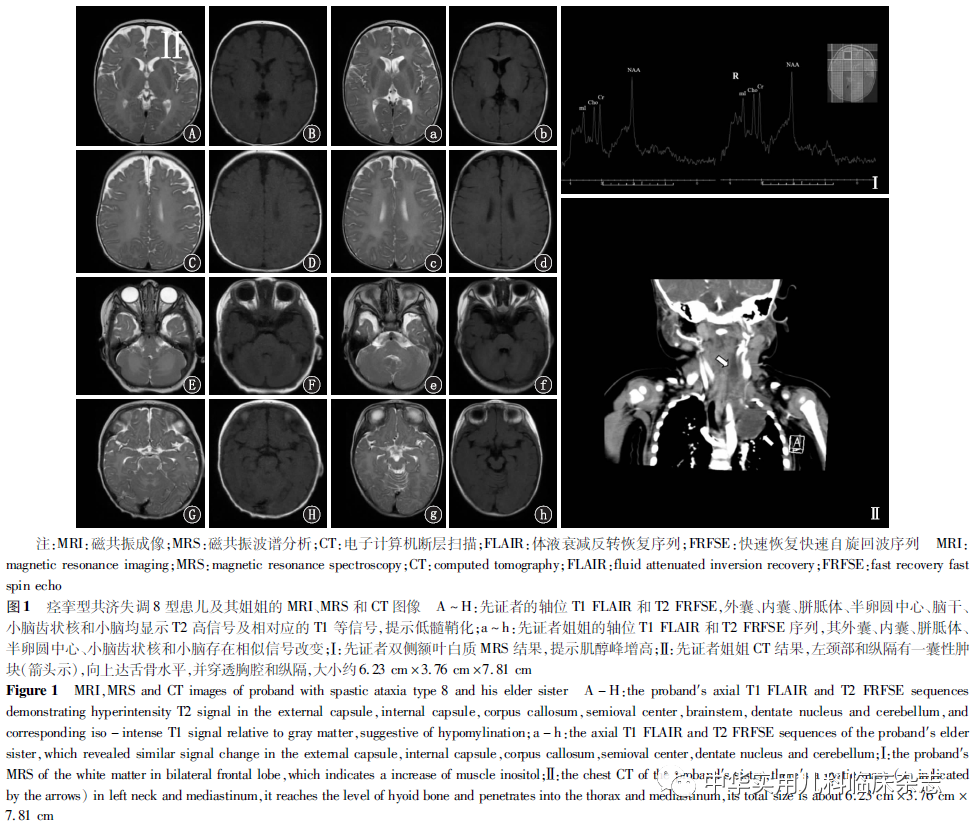

临床资料回顾性个案研究。先证者,男,2岁7个月,4月龄时家属发现其不会竖头、抬头,7月龄时因仍不会竖头、抬头,不会翻身,不会独坐就诊。患儿系第4胎,第6产,足月剖宫产,出生时无产伤和窒息史,出生后听力筛查提示右耳听力障碍,6月龄时听力诊断提示双侧感音神经性耳聋。父母体健,非近亲结婚,患儿有2个姐姐和1个哥哥,其中1个姐姐有全面发育迟缓病史,余兄姐发育正常。患儿一般查体:生命体征平稳,心肺腹无特殊;专科查体:头围45 cm,前囟未闭,大小约2 cm×2 cm,竖头不稳,头控差,俯卧位不能抬头,能侧翻身,不能独坐,双手握拳,拇指内收,能吃手,双上肢肌张力正常,双下肢肌张力偏高(Ⅰ 级,改良Ashworth量表测量),四肢肌力Ⅳ 级;双眼倒睫,双眼球水平震颤,对视差,追视追听欠灵活,能微笑,不能笑出声,发音少。辅助检查:血常规、血气、生化及代谢相关检验(包括串联质谱、乳酸、血浆氨等)均未见明显异常;听力检查提示双侧感音神经性听力丧失,但中耳和内耳磁共振成像(MRI)未见结构异常。眼底检查提示中枢性视力低下、双眼屈光不正、右眼视网膜变性。头颅MRI 示大脑半球、脑干和小脑白质弥漫性T2高信号和相对应区域的T1低-等信号;磁共振波谱分析(MRS)提示肌醇(mI)峰升高,胆碱(Cho)、肌酐(Cr)和N-乙酰天门冬氨酸(NAA)无明显异常(图1A~H、图1Ⅰ)。患儿脑电图结果未见异常。先证者姐姐在出生1年内即出现了严重全面性发育迟缓和痉挛性四肢瘫痪,现6岁,仍竖头不稳,俯卧位头能抬离床面,仍无有意义发音,且也有听力障碍。其母在其孕期期间曾有“先兆流产”史,但出生史无特殊。头颅MRI表现与先证者相似(图1a~h),但未行MRS检查。另外,先证者姐姐胸部CT提示左颈部及纵隔有一囊性肿块,被认为是淋巴管瘤(图1Ⅱ),但未进行活检证实。先证者的全基因组测序结果提示10号染色体上存在NKX6-2基因纯合突变c.234dup(p.Leu79Alafs*?),一代验证提示其父母均为杂合突变(图2)。这种存在于NKX6-2基因1号外显子上的纯合突变会造成终止密码子丢失,影响蛋白质翻译的终止,从而导致蛋白功能丧失。先证者姐姐未接受基因检测。本研究通过广东省妇幼保健院医学伦理委员会批准(批准文号:202001226),患儿监护人知情同意,并签署知情同意书。

讨论SPAX8是2017年被Chelban等[4]首次报道并描述的一种常染色体隐性遗传病。根据发病年龄,患者预后可分为2种结局:严重类型即在新生儿期起病并进展迅速,表现为眼球震颤、严重痉挛性四肢瘫伴关节挛缩和脊柱侧弯、听力损害和视力损害,在儿童早期死亡;较轻类型即表现为在出生第1年内能正常获得早期运动里程碑,以后出现缓慢进展的伴锥体征阳性的复杂型痉挛性共济失调以及伴发育里程碑丧失的小脑体征[10]。截至2020年3月24日,已有36例共涉及11种NKX6-2基因突变类型的SPAX8病例报道,而SPAX8基因型-表型的相关性尚不明确。Chelban等[4]提出NKX6-2双等位基因截断突变似乎与小脑萎缩有关,并可能提示预后不良,而双等位基因截断突变和错义突变可能与年龄相关性表型有关。另外,同源盒区域中的双等位致病突变被认为与严重表型相关[4-5,7,9]。本研究总结了目前已报道的NKX6-2基因12种突变类型(包括本例患儿)和其涉及的表型,发现37例患者均出现运动发育迟缓,但其中6例c.121A>T纯合突变的患者认知功能正常,因此推测,NKX6-2基因的c.121A>T纯合突变可能与更好的认知结局相关。在已报道的案例中,大部分来自阿拉伯(17/36例),本研究患儿是第1例报道的中国人,其携带了一个未被报道的纯合突变c.234dup (p.Leu79Alafs*?)。与以往报道不同的是,这种存在于NKX6-2基因1号外显子上的纯合突变会造成终止密码子丢失,影响蛋白质翻译的终止,从而导致蛋白功能丧失。结合患儿的临床症状和影像学表现,SPAX8诊断成立。在已报道的患者中,30例有眼部症状,包括眼球震颤(25/30例)、斜视(6/30例)、视盘苍白(2/30例)、向下扫视(6/30例)、眼球活动受限(2/30例)、视神经苍白(4/30例)和视力损害(8/30例)。而本例患儿的眼部表型除眼球震颤外,还有倒睫、双眼屈光不正和右眼视网膜变性等尚未报道过的表型。因此,考虑到该病眼部受累的高发生率,建议此类患者应接受详细的眼科检查。SPAX8最常见的头颅MRI表现为累及脑室周围、苍白球、外囊、内囊、小脑脚、脑桥、中脑、丘脑和小脑齿状核等部位的髓鞘化低下。本研究中先证者MRI表现为与其临床表现相一致的双侧大脑、脑干和小脑白质对称性弥漫性受累。此外,先证者MRS结果显示mI峰升高,而Cho、Cr和NAA无明显异常,这些结果与Takanashi[11]提出的人类低髓鞘化疾病中的MRS特征相符。但由于其他已报道病例中缺乏MRS资料,目前尚不清楚SPAX8的MRS特征与其他低髓鞘化疾病是否存在差别。另外,先证者其中一位有类似症状的姐姐由于未进行基因检测,无法明确做出SPAX8的诊断,但由于高度怀疑其为SPAX8,本研究仍对其临床表现进行了描述。并且其胸部CT提示左颈部和纵隔淋巴管瘤的可能,这是之前案例从未报道过的。这个可疑的表型对临床医师可能有提示作用,即SPAX8患者有必要进行胸片或胸部超声检查来筛查类似病变。综上,SPAX8的特征与其他类型的低髓鞘化性脑白质营养不良相似,主要表现为全面发育迟缓、痉挛性四肢瘫及头颅MRI脑实质对称性弥漫性的T2高信号和T1低-等信号,部分伴听力障碍或视力损害。本研究报道了第1例因NKX6-2基因c.234dup(p.Leu79Alafs*?)纯合突变所致的SPAX8患儿,扩大了该病的基因谱;同时也是该病第1例报道的中国患儿,此患儿与其姐姐新报道的眼部症状和胸部CT发现可能有助于扩展NKX6-2突变的表型谱,作者建议临床诊断SPAX8的患者应进行更详细的眼科检查和胸片或胸部超声筛查。并且,综合分析已报道的案例,我们认为NKX6-2基因的c.121A>T纯合突变可能与更好的认知结局相关。另外,建议临床医师在遇到此类不能确诊的患者时,应积极进行基因检查来帮助临床诊断。